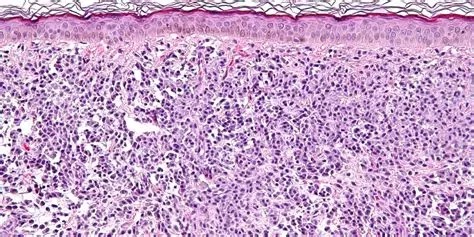

Immagine: una delle caratteristiche clinico-patologiche rappresentativa della mastocitosi